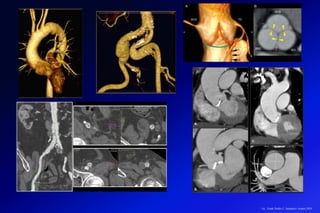

El desarrollo de los TCMD ha permitido realizar una serie de procedimientos a

nivel cardiovascular (angiografía cardiaca, aortica y sistema vascular periférico.)

que permiten realizar en la salas de hemodinámicas procedimientos como

remplazo de la válvula aortica, colocación de stents por aneurismas o disección

de la aorta.